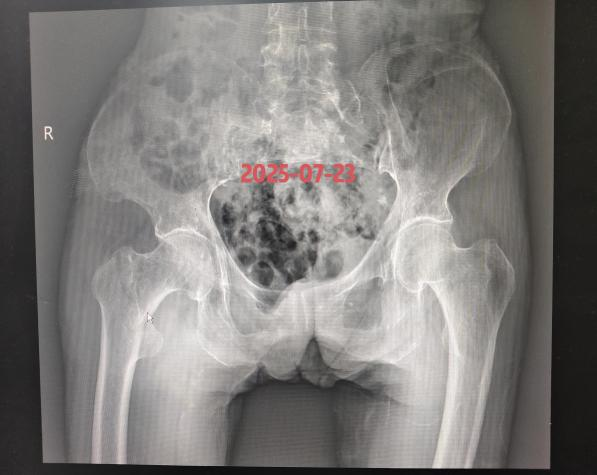

近期,85岁李奶奶,因摔倒致右股骨粗隆间粉碎性骨折,来我院就诊。

患者高龄,并发高血压、冠心病及肺部基础疾病,我院骨科团队迅速联合内科主任、麻醉科医师进行多学科会诊,评估病情,最终确定在腰麻下行右股骨粗隆间骨折闭合复位髓内钉内固定手术方案。安庆市第一人民医院骨科何流教授率领王亮主治医师通过 3 个小切口完成骨折复位与固定,手术顺利,术后恢复良好,术后5天李奶奶可以翻身自行坐起,目前在助行器辅助下部分负重行走。